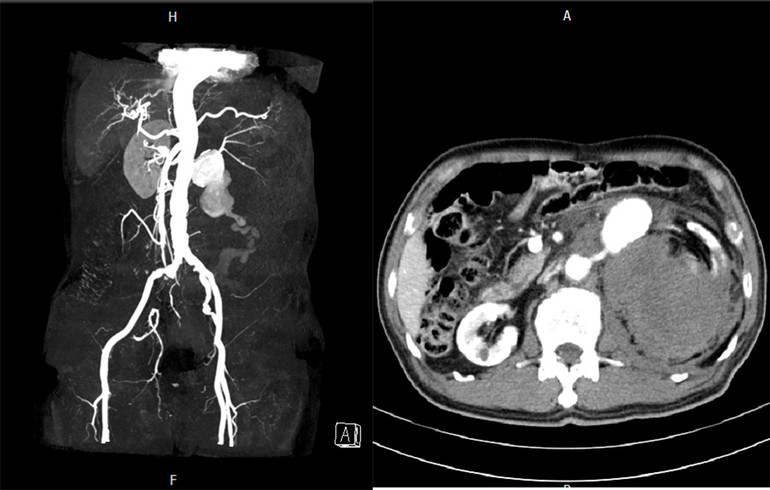

Tổn thương của bệnh nhân.

Người bệnh Hoàng V.I 77 tuổi trú tại An Đạo, Phù Ninh, Phú Thọ nhập viện đơn vị Phẫu thuật tim mạch - Lồng ngực - Trung tâm Tim mạch phẫu thuật cấp cứu, Bệnh viện Đa khoa tỉnh Phú Thọ trong tình trạng đau dữ dội mạn sườn trái, kèm theo dấu hiệu sốc. Người bệnh được siêu âm và chụp cắt lớp vi tính bụng phát hiện vỡ phình động mạch thận trái. Tình trạng sốc tăng dần, huyết áp tối đa còn 50 mmHg.

Ngay lập tức, người bệnh được tiến hành các biện pháp hồi sức cấp cứu tích cực. Khởi động hệ thống báo động đỏ hội chẩn toàn bệnh viện. Người bệnh được chỉ định phẫu thuật cấp cứu khống chế, lấy bỏ khối phình và thắt động mạch thận trái, lấy khoảng 2.000 ml máu tụ sau phúc mạc.